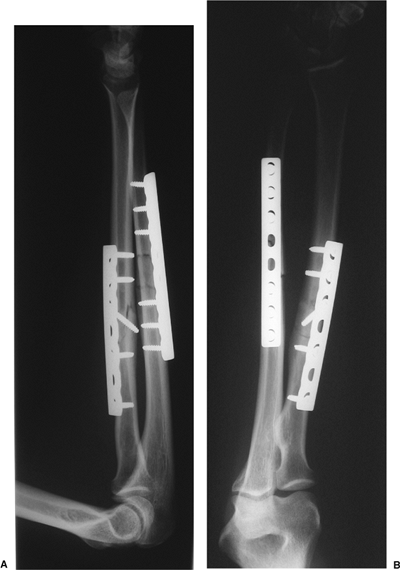

Figure 10.20. A,B.

A both-bone forearm fracture treated with compression plating of the radius and bridge plate fixation of the ulna is shown. A long plate with minimal screw insertion was utilized to minimize bone devitalization. |